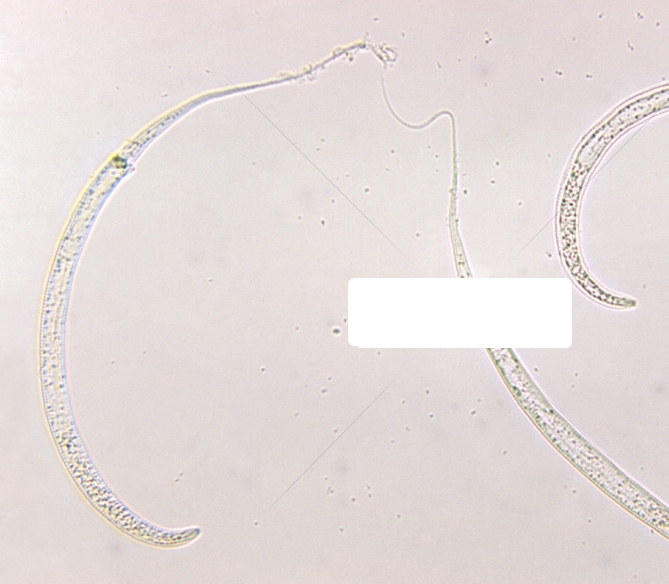

据了解,龙线虫俗称"几内亚虫".是能寄生在哺乳动物体深部的大型线虫.

龙线虫,俗称"几内亚虫",最早见于几内亚,线虫纲,龙线科,是寄生在哺乳